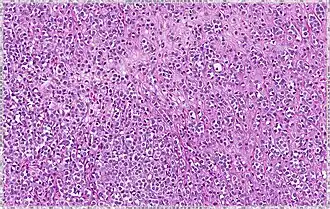

| Classical | 40% | Round or ovoid cells with little cytoplasm in a single-file infiltrating pattern, sometimes concentrically giving a targetoid pattern |

|

| Pleomorphic | Classical-appearing but with pleomorphic cells. It may include signet-ring cells, or plasmacytoid cells (pictured) which have abundant cytoplasm and eccentric nuclei. | ![]() |

Histopathology of invasive lobular carcinoma (ILC), next to lobular carcinoma in situ (LCIS) -

Invasive lobular carcinoma demonstrating a predominantly lobular growth pattern -

Lobular breast cancer. Single file cells and cell nests. -

ILC may be subtle on low magnification (left). Higher magnification (right) shows invasive growth pattern and vesicular nuclei with prominent nucleoli.